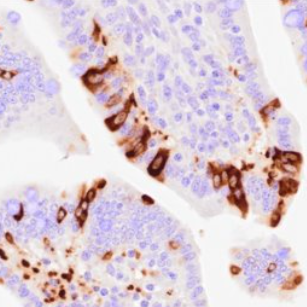

Public workspaceImmunohistochemical detection of porcine epidemic diarrhea virus (PEDV) in formalin-fixed, paraffin-embedded (FFPE) pig tissues

An immunohistochemistry (IHC) staining protocol for in situ identification of porcine epidemic diarrhea virus (PEDV) in formalin-fixed, paraffin-embedded (FFPE) tissue.